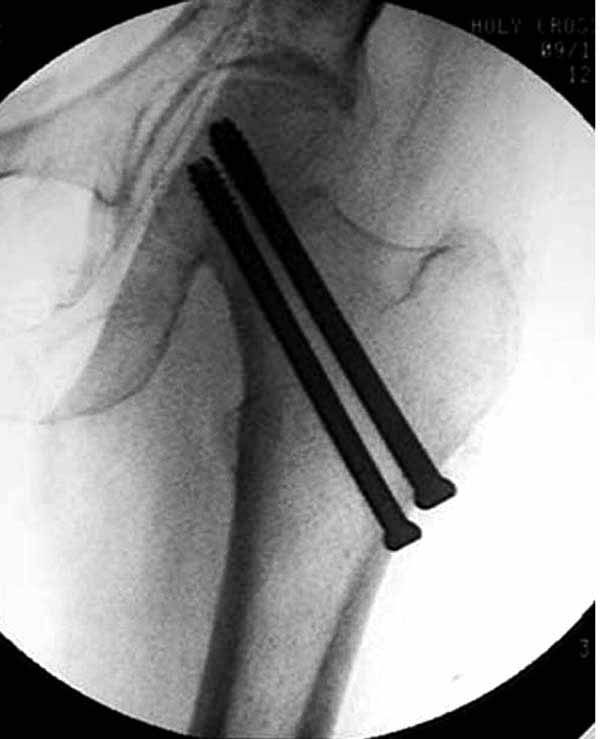

Как отметили коллеги, необходимо обратить внимание на последовательность введения каннюлированных шурупов. Рекомендуется введение в форме “V”, т.е основанием вниз, потому что в другой последовательности за счет увеличения стресса латерального кортекса имеется риск перелома. За редким исключением удается установить Guide wire с первой попытки и многоразовые пробы спицей увеличивают стресс. Небольшая травма может привести к перелому.

Работа Burstein AH and Wright TM: Fundamentals of Orthopaedic Biomechanics. Williams & Wilkins, Baltimore, pp. 160-169, 1994 доказывает, что шурупы, введенные на уровне малого вертела или ниже, приводят к осложнению. Введенные шурупы под 135 и больше градусов в 20% осложнились подвертельными переломами бедра.